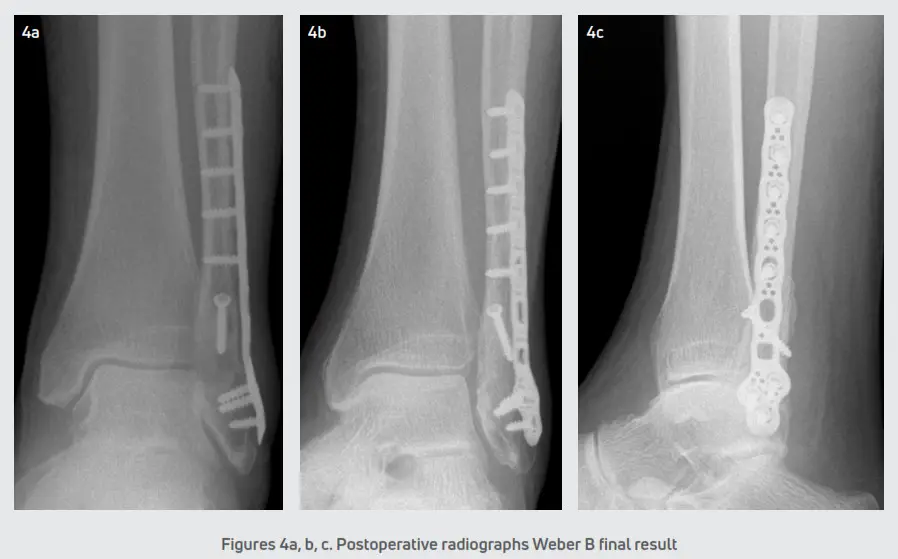

The incisions were closed in a standard layered fashion and a sterile, compressive dressing was applied. All patients were immobilized with a posterior splint and were initially non-weight bearing. Patients were seen for the first postoperative visit within 5-6 days for a wound evaluation. A sterile dressing and posterior splint were reapplied and patients returned at two weeks for suture removal. The postoperative course consisted of non-weight bearing in a posterior splint for 2-3 weeks. In ankle fractures with a stable syndesmosis (Figure 4), patients were transitioned into a CAM boot at 3 weeks and began protected partial weight-bearing with physical therapy. After 6 weeks, patients were transitioned to a supportive athletic shoe with an ankle brace and the final follow-up was at 12 weeks. In ankle fractures that required syndesmotic repair (Figure 5), patients were transitioned into a CAM boot and began protected partial weight-bearing at approximately 8-10 weeks. Patients were progressed into normal shoe gear at 12 weeks and aggressive physical therapy. Patients were discharged at 4-6 months and followed up as needed.